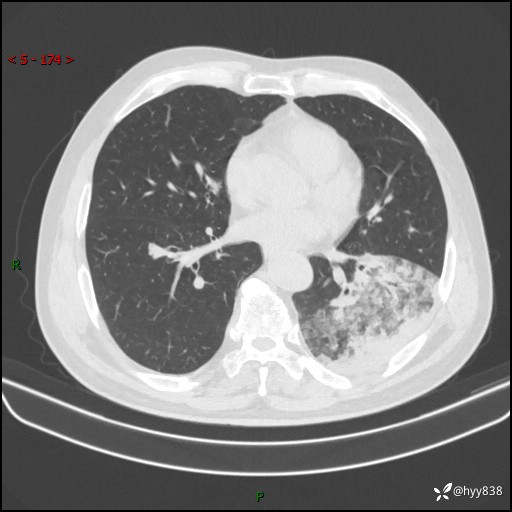

59岁/男,发热伴咳嗽3天。白班偶遇,“大叶性肺炎”,病原体挑战---结果公布~

【患者信息】:59岁/男

【主诉】:发热伴咳嗽3天

【检查】:胸部CT平扫